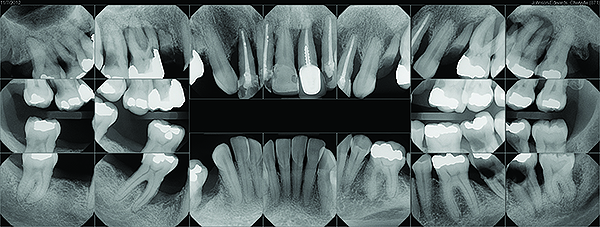

Fig 4. Periodontal disease in a patient with halitosis.

Figure 4

A rotten egg or cabbage smell is indicative of VSC being the main cause of halitosis. These compounds are usually associated with periodontal disease (Figure 3 and Figure 4) and/or tongue coating. Patients suffering from periodontitis or peri-implantitis require professional periodontal treatment in order to eliminate periodontal pathogens.5 Following a professional scaling and root planing appointment, Gram-negative anaerobic bacteria responsible for causing periodontal disease and producing VSC are reduced.5 This, in turn, encourages repopulation with Gram-positive cocci and bacterial rods that are associated with oral health.

Evaluation of the patient’s full mouth series of radiographs revealed signs of mild periodontal bone loss and a large carious lesion/defective restoration on tooth No. 19. A treatment plan was devised that included oral hygiene instructions, scaling/root planing, root canal treatment on No. 19, crown fabrication on No. 19, and re-evaluation 4 to 6 weeks later. During the re-evaluation appointment, oral hygiene was shown to be slightly improved, and a 3-month periodontal maintenance interval was suggested (Figure 8). The patient reported a significantly decreased degree of malodor and was very satisfied.